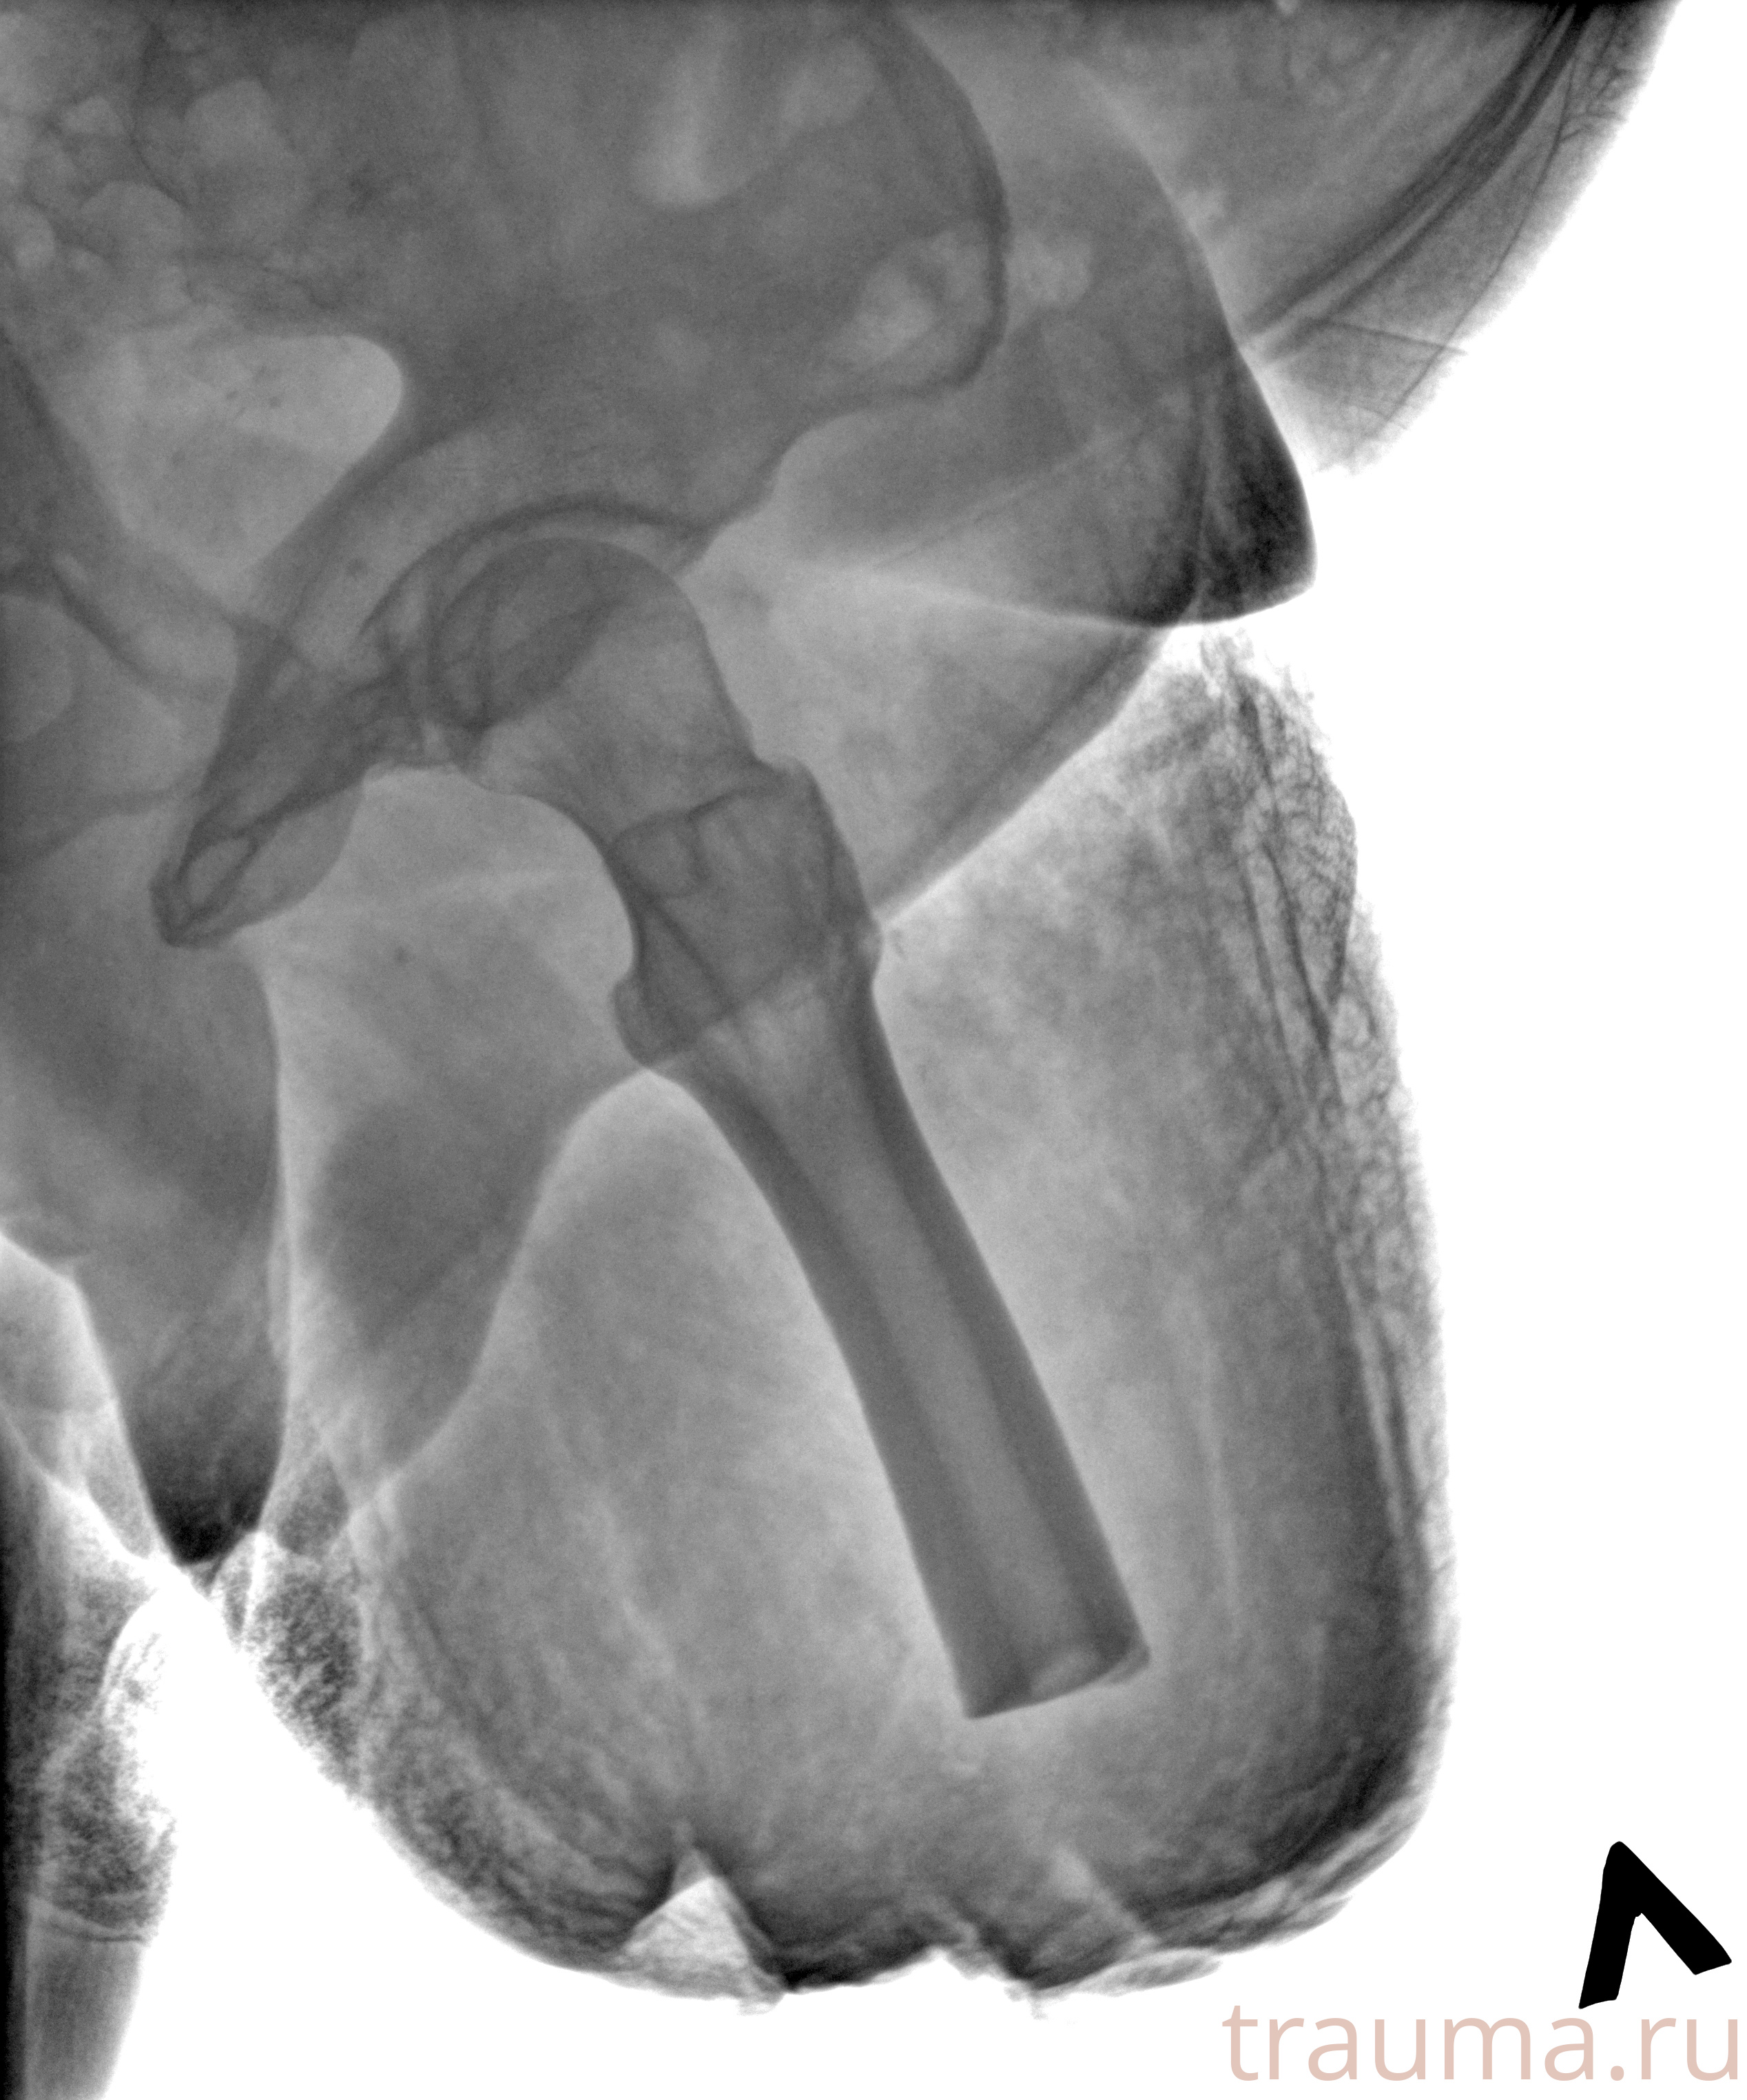

Рентгенограммы

Рентген на дому: по вашему адресу приезжает врач-рентгенолог, травматолог-ортопед с мобильным рентгеновским аппаратом, проводит диагностику травмы или заболевания, делает необходимые рентгенограммы, дает рекомендации по дальнейшему лечению. Получить качественные снимки в домашних условиях возможно благодаря уникальной методике, разработанной МосРентген Центром для института  Склифосовского